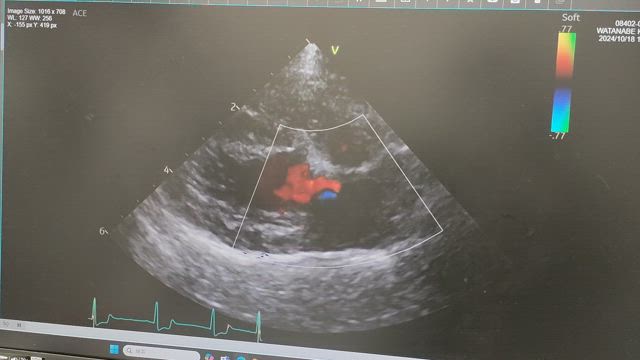

心臓手術して一年経ちました。

術後6カ月検診